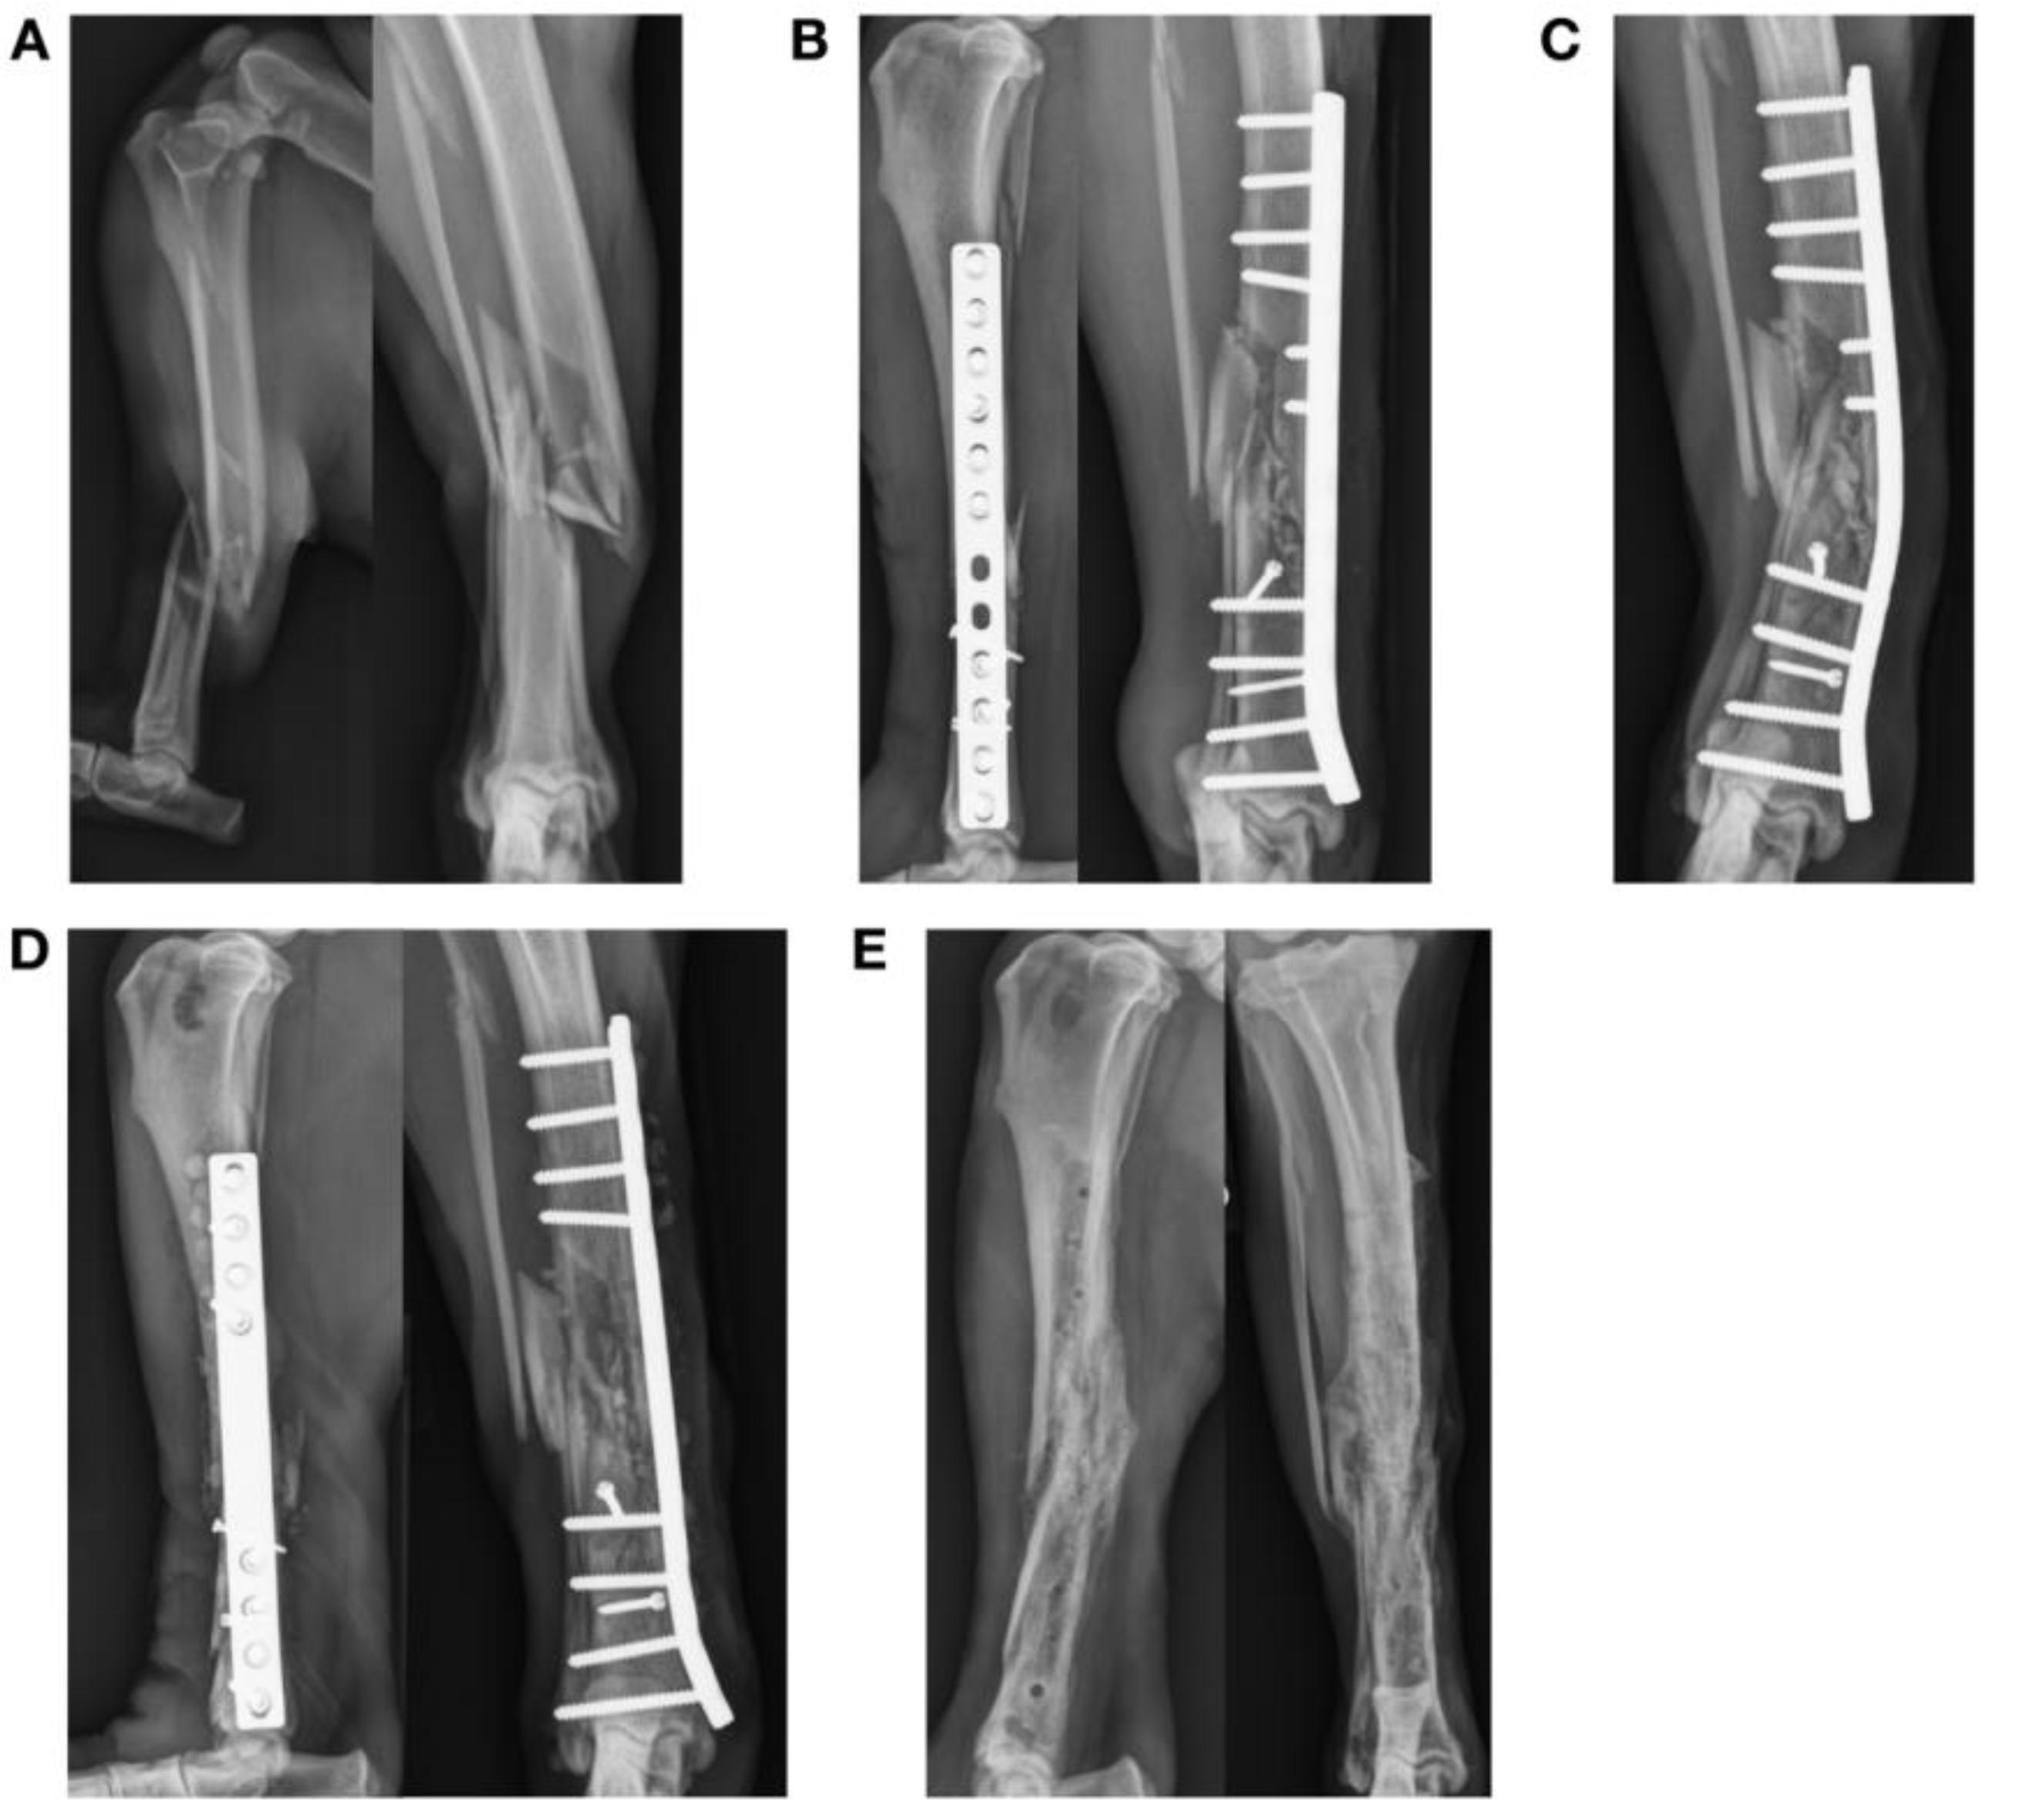

Figure 4.

Failure of a bridging plate construct used to treat an open comminuted right tibial diaphyseal fracture in an eight-year-old Labrador retriever (A,B). The fracture was stabilized with a 12-hole 3.5 mm DCP (AMI = 46.7 mm4) and 2 independent 2.4 mm lag screws with 10 cortices engaged above the fracture and 12 cortices below the fracture. Two independent 2.4 mm cortical screws were placed in lag fashion. Two holes over the fracture site were left empty and the fracture was grafted with autogenous cancellous bone graft from the right proximal tibia. Plate span was 72%. The dog was discharged without external coaptation. (C) Bending of the plate was found at the level of the fracture and empty screw holes at 2 weeks, causing tibial valgus. (D) The fracture construct was revised using an 8-hole 4.5 mm narrow limb-lengthening plate (AMI = 54.9 mm4) and the fracture was re-grafted with autogenous cancellous bone. (E) Implant removal was performed after clinical union.